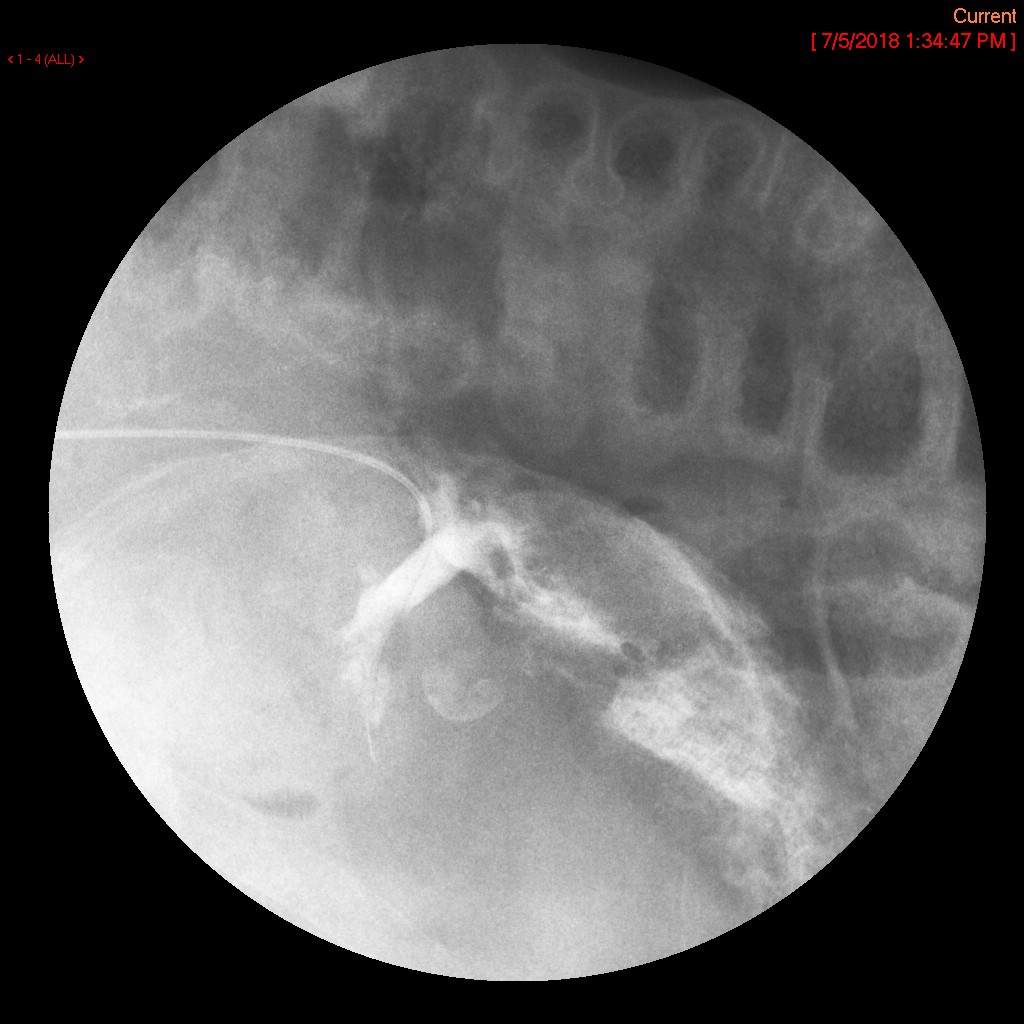

- The gynecologist will begin injecting contrast material into the uterus. Obtain images periodically throughout the procedure (usually at the direction of the gynecologist). The images should include the uterine cavity filled with contrast material, bilateral fallopian tubes filled with contrast material, and spillage and dispersion of contrast material into the peritoneal cavity (image 1) (image 2) (image 3) (image 4) (image 5).

- It may be necessary to place the patient into either the right lateral or left lateral oblique postion to define the anatomy more clearly.

- Spillage into the peritoneal cavity is not always seen. If this occurs during the examination, be sure to note it in the dictation.